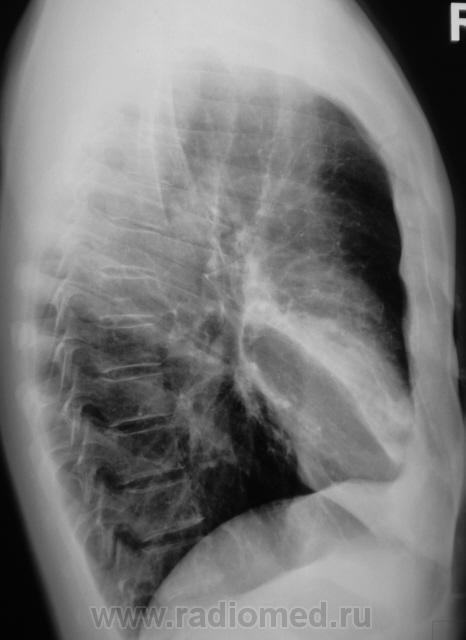

Еще контроль через 1 месяц.